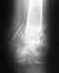

Заочно можно лишь сказать, что если перелом действительно без смещения, никакие ортезы, в том числе названный, не нужны. К месяцу перелом пятки без смещения (еще раз, если это действительно такой перелом, снимок Вы не показываете) уже сросся, иммобилизация не нужна, можно и нужно начинать движения и увеличивать нагрузку.